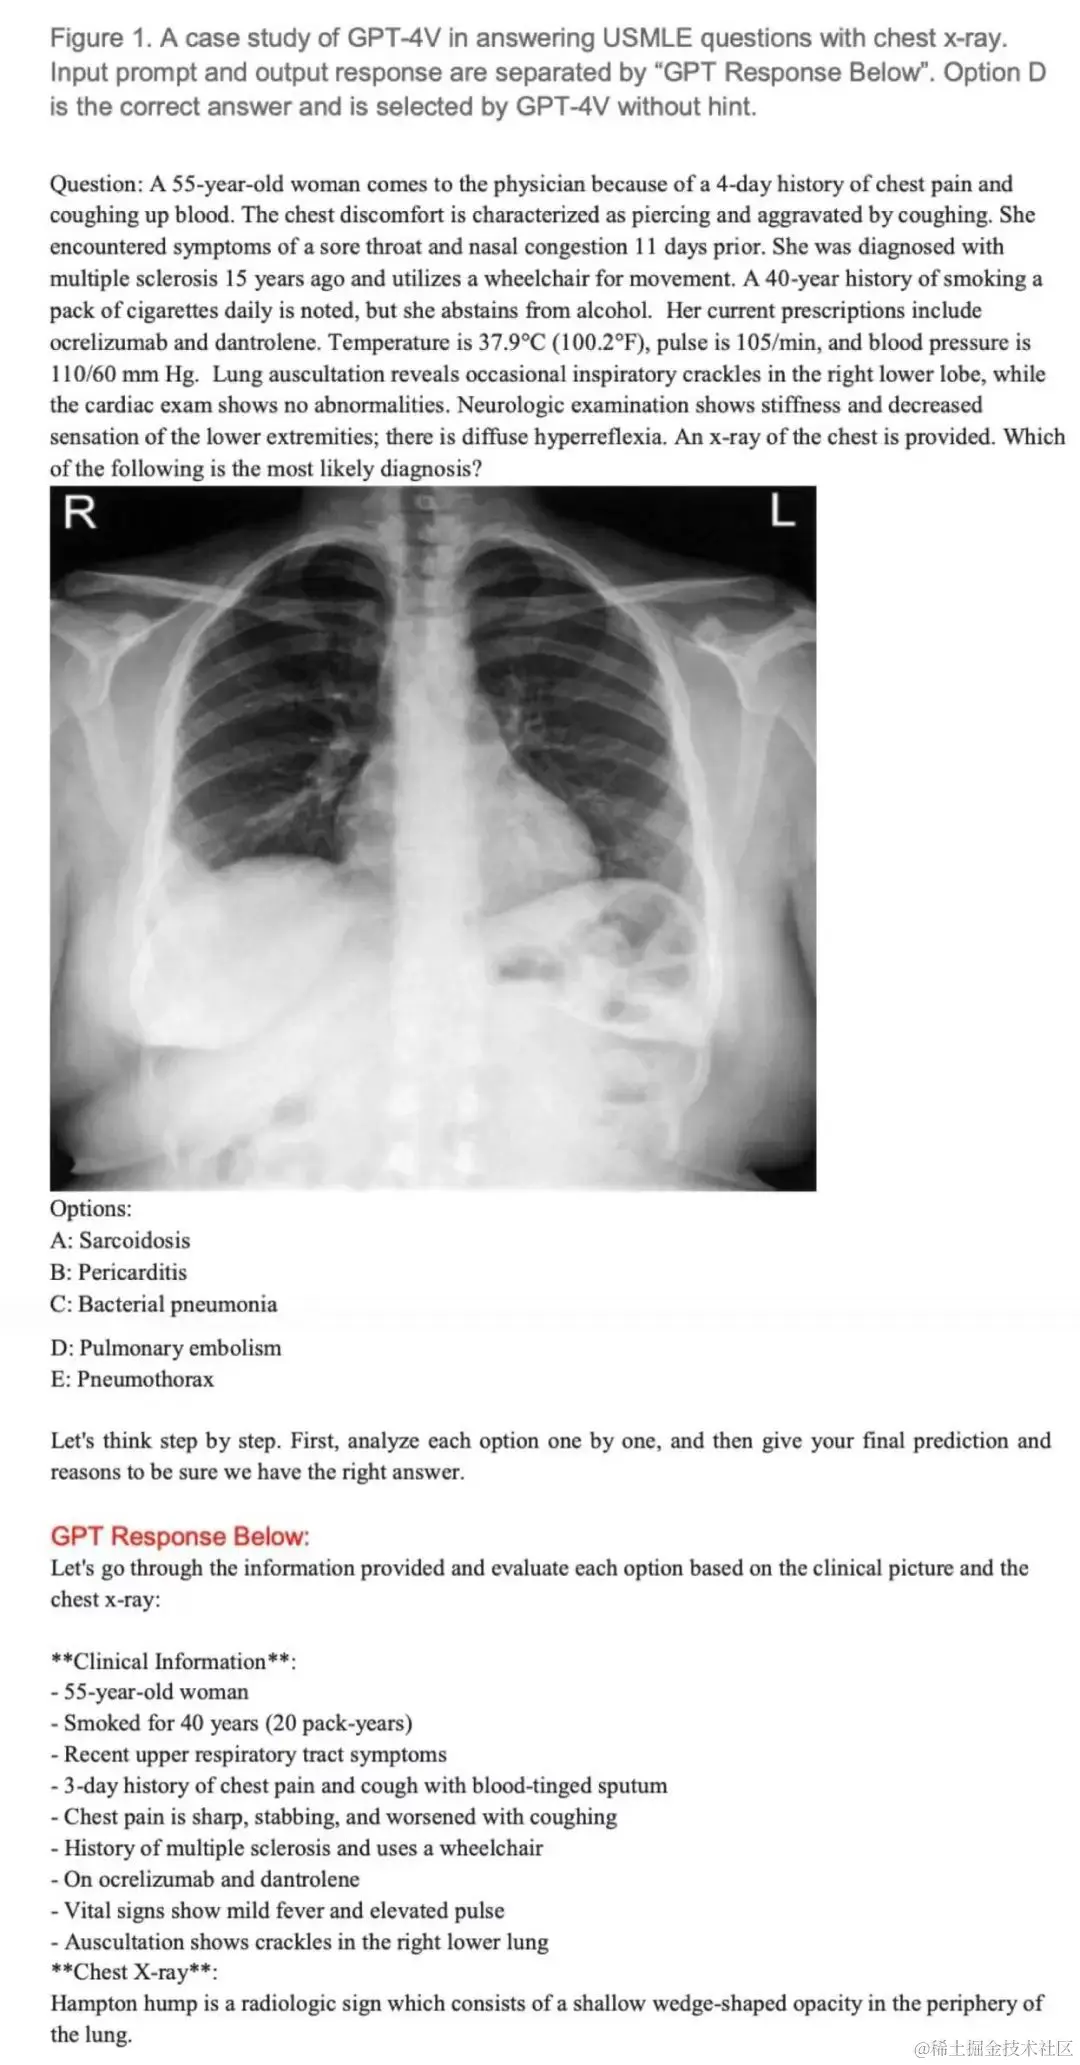

图片 用美国医学执照考试(USMLE)中包含图像的考题测试 GPT-4V。